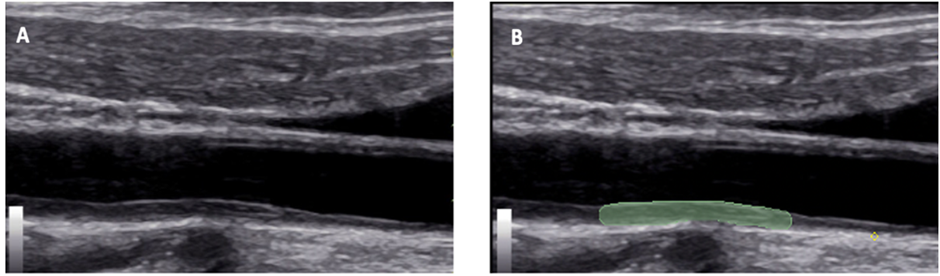

All carotid ultrasound examinations were performed at the bedside using GE Logic ultrasound systems equipped with 12L-RS linear transducers (General Electric®). Examinations were conducted by three radiologists with 4–10 years of experience, with each patient evaluated by at least two operators. Images were stored in DICOM format. B-mode images were acquired in axial and longitudinal planes. The carotid intima–media complex was evaluated on the posterior wall of the common carotid artery in plaque-free segments. IMC thickness was defined as the distance between the lumen–intima and media–adventitia interfaces and classified as thickened according to ELSA-Brasil criteria [12,13] (Figure 1).

Figure 1: B-mode ultrasound image of the right carotid artery in the longitudinal direction of a study patient with severe Covid-19, showing in A the thickening of the intima-media complex (arrowhead) and in B the delimitation of the region of interest (green marking).